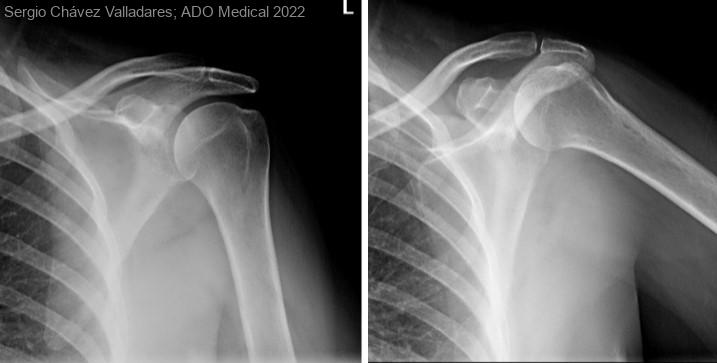

Bursitis subacromiodeltoidea tras administración de vacuna contra el SARS-COV2.

Mujer de 64 años con antecedentes de diabetes mellitus, hernia de hiato, fibromialgia y coxartrosis bilateral. Es derivada desde atención primaria por omalgia izquierda de tres meses de evolución, cuyo inicio relacionaba la paciente con...